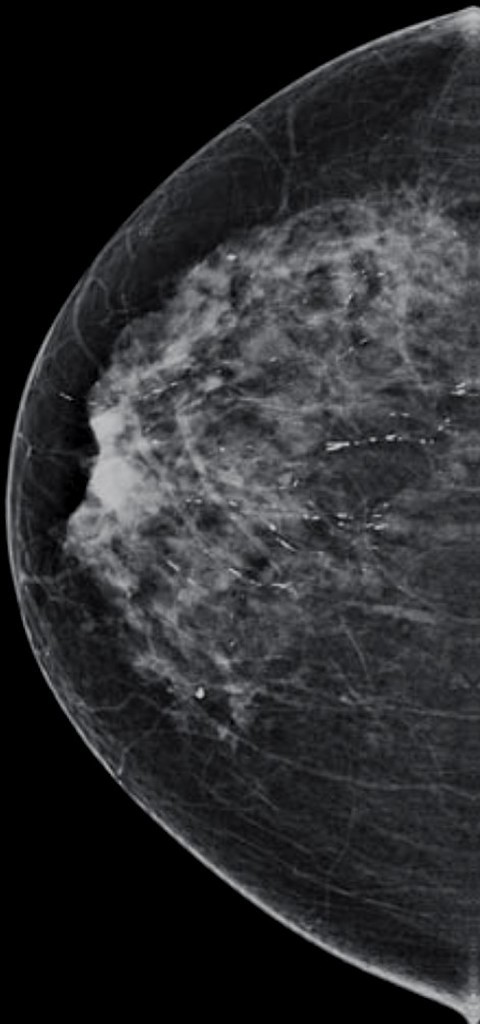

Normal fibroglandular tissue, island

feathery appearance with intervening lucent areas of this finding suggests that this is an island of glandular tissue rather than a mass, and its stability would support a BI-RADS 2 (benign) or BI-RADS 1 (negative) assessment

**here called a focal asymmetry bc normal CC view doesn’t image this portion of the breast-need an extended CC view